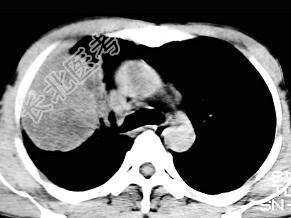

- 单项选择题根据所提供的图像,最可能的诊断是 ( )

A、肺内软骨肉瘤

B、胸膜间皮瘤

C、球形肺炎

D、机化性肺炎

E、局限性不张